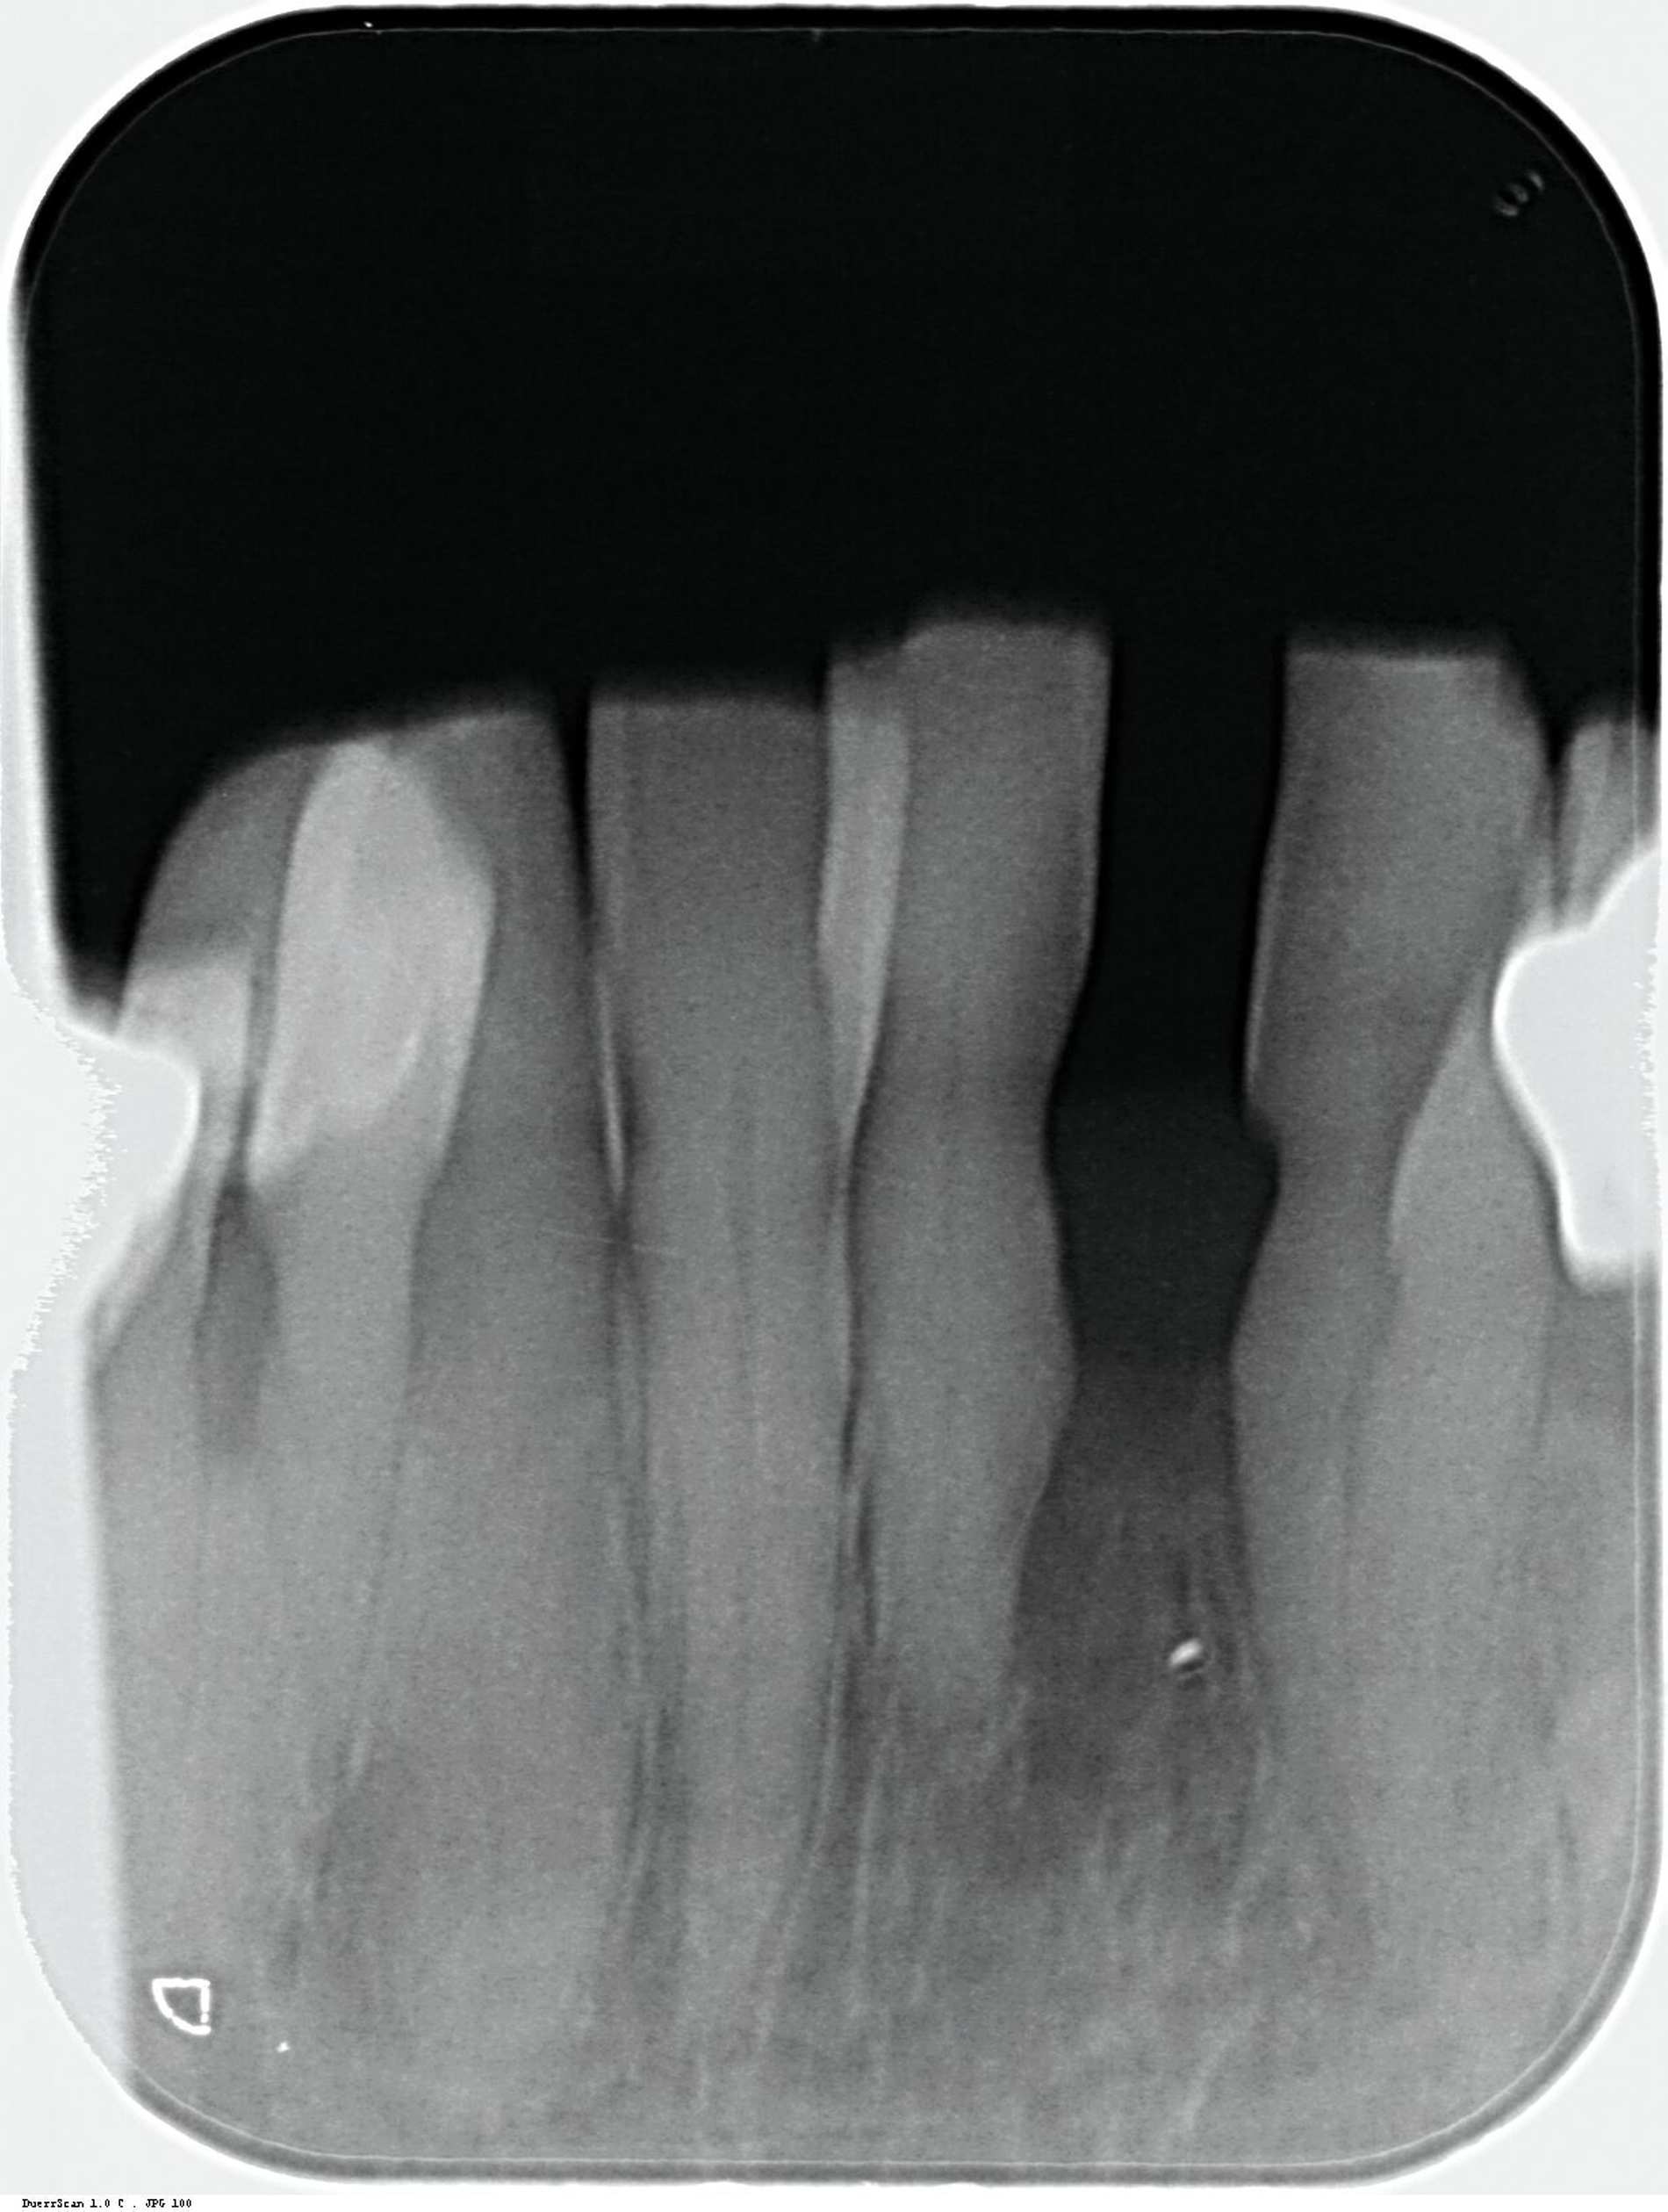

Da anhand eines Zahnfilms festgestellt worden war, dass der Zahn 31 – vermutlich aufgrund einer Paro-Endo-Läsion – eine apikale Aufhellung zeigte, war bereits die Extraktion mit anschließender Umarbeitung und adhäsiver Wiedereingliederung des extrahierten Zahnes als Option angesprochen worden. Kurz vor dem vereinbarten Eingriff meldete sich die Patientin telefonisch, um sich zu erkundigen, ob sie den Termin denn überhaupt noch benötige, da der betroffene, gelockerte Zahn 31 in der Unterkieferfront beim Essen von selbst herausgefallen sei und sie ihn bereits entsorgt habe. Schmerzen, eine Schwellung oder Nachblutungen verneinte die Patientin. Sie wurde gebeten, den vereinbarten Termin am Folgetag dennoch wahrzunehmen, mindestens zur Kontrolle der Wunde, gegebenenfalls zur Planung der Weiterversorgung (Abbildungen 5 und 6).

Nach der erneuten Untersuchung am Folgetag wurden der Patientin die möglichen Therapieoptionen in der neu entstandenen Situation erläutert. Denkbar waren grundsätzlich ein prothetischer Ansatz, aus konservierender Sicht der Lückenschluss mittels adhäsiver Zahnverbreiterung und der Lückenschluss mittels Ersatzzahn.